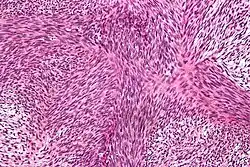

| Micrograph of malignant peripheral nerve sheath tumour with the typical herringbone pattern. H&E stain. | |